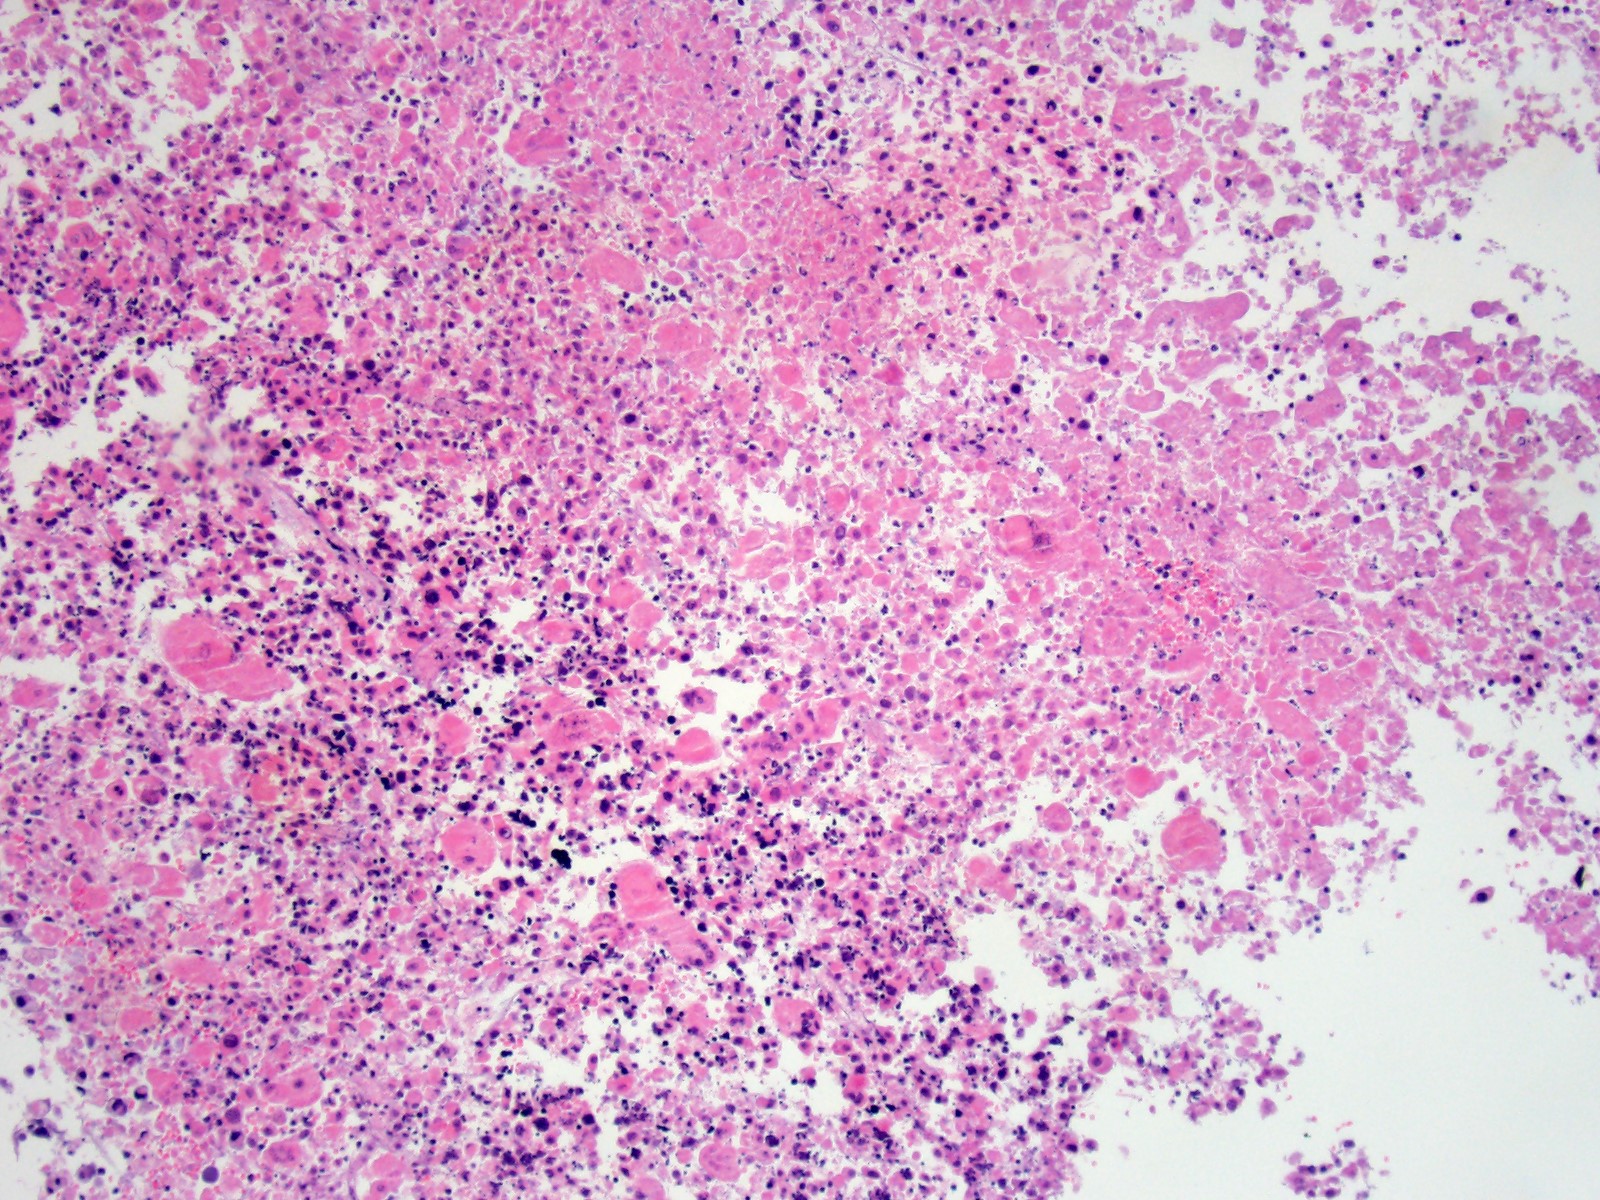

Higher magnification view of necrotic debris, degenerate neutrophils, fibrin and hemorrhage.